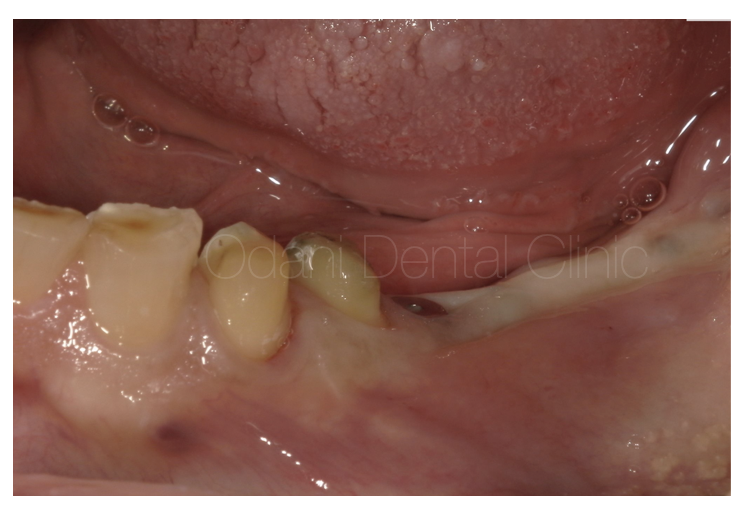

60代 男性 弱った歯の感染の影響で、抜歯後に大きな凹みを生じている症例です。

事前のCT画像によるシミュレーション通り、インプラント体を埋入するとインプラントのネジが大きく露出した状態(左写真)です。骨を作りたいところにチタン性のピンをテントの支柱のようなイメージで植立し、骨移植材を用いて骨造成を図りました(右写真)。

一次手術治癒後の状態です。骨造成を図ったことで、もともとの歯ぐきのヘコみが改善しました。